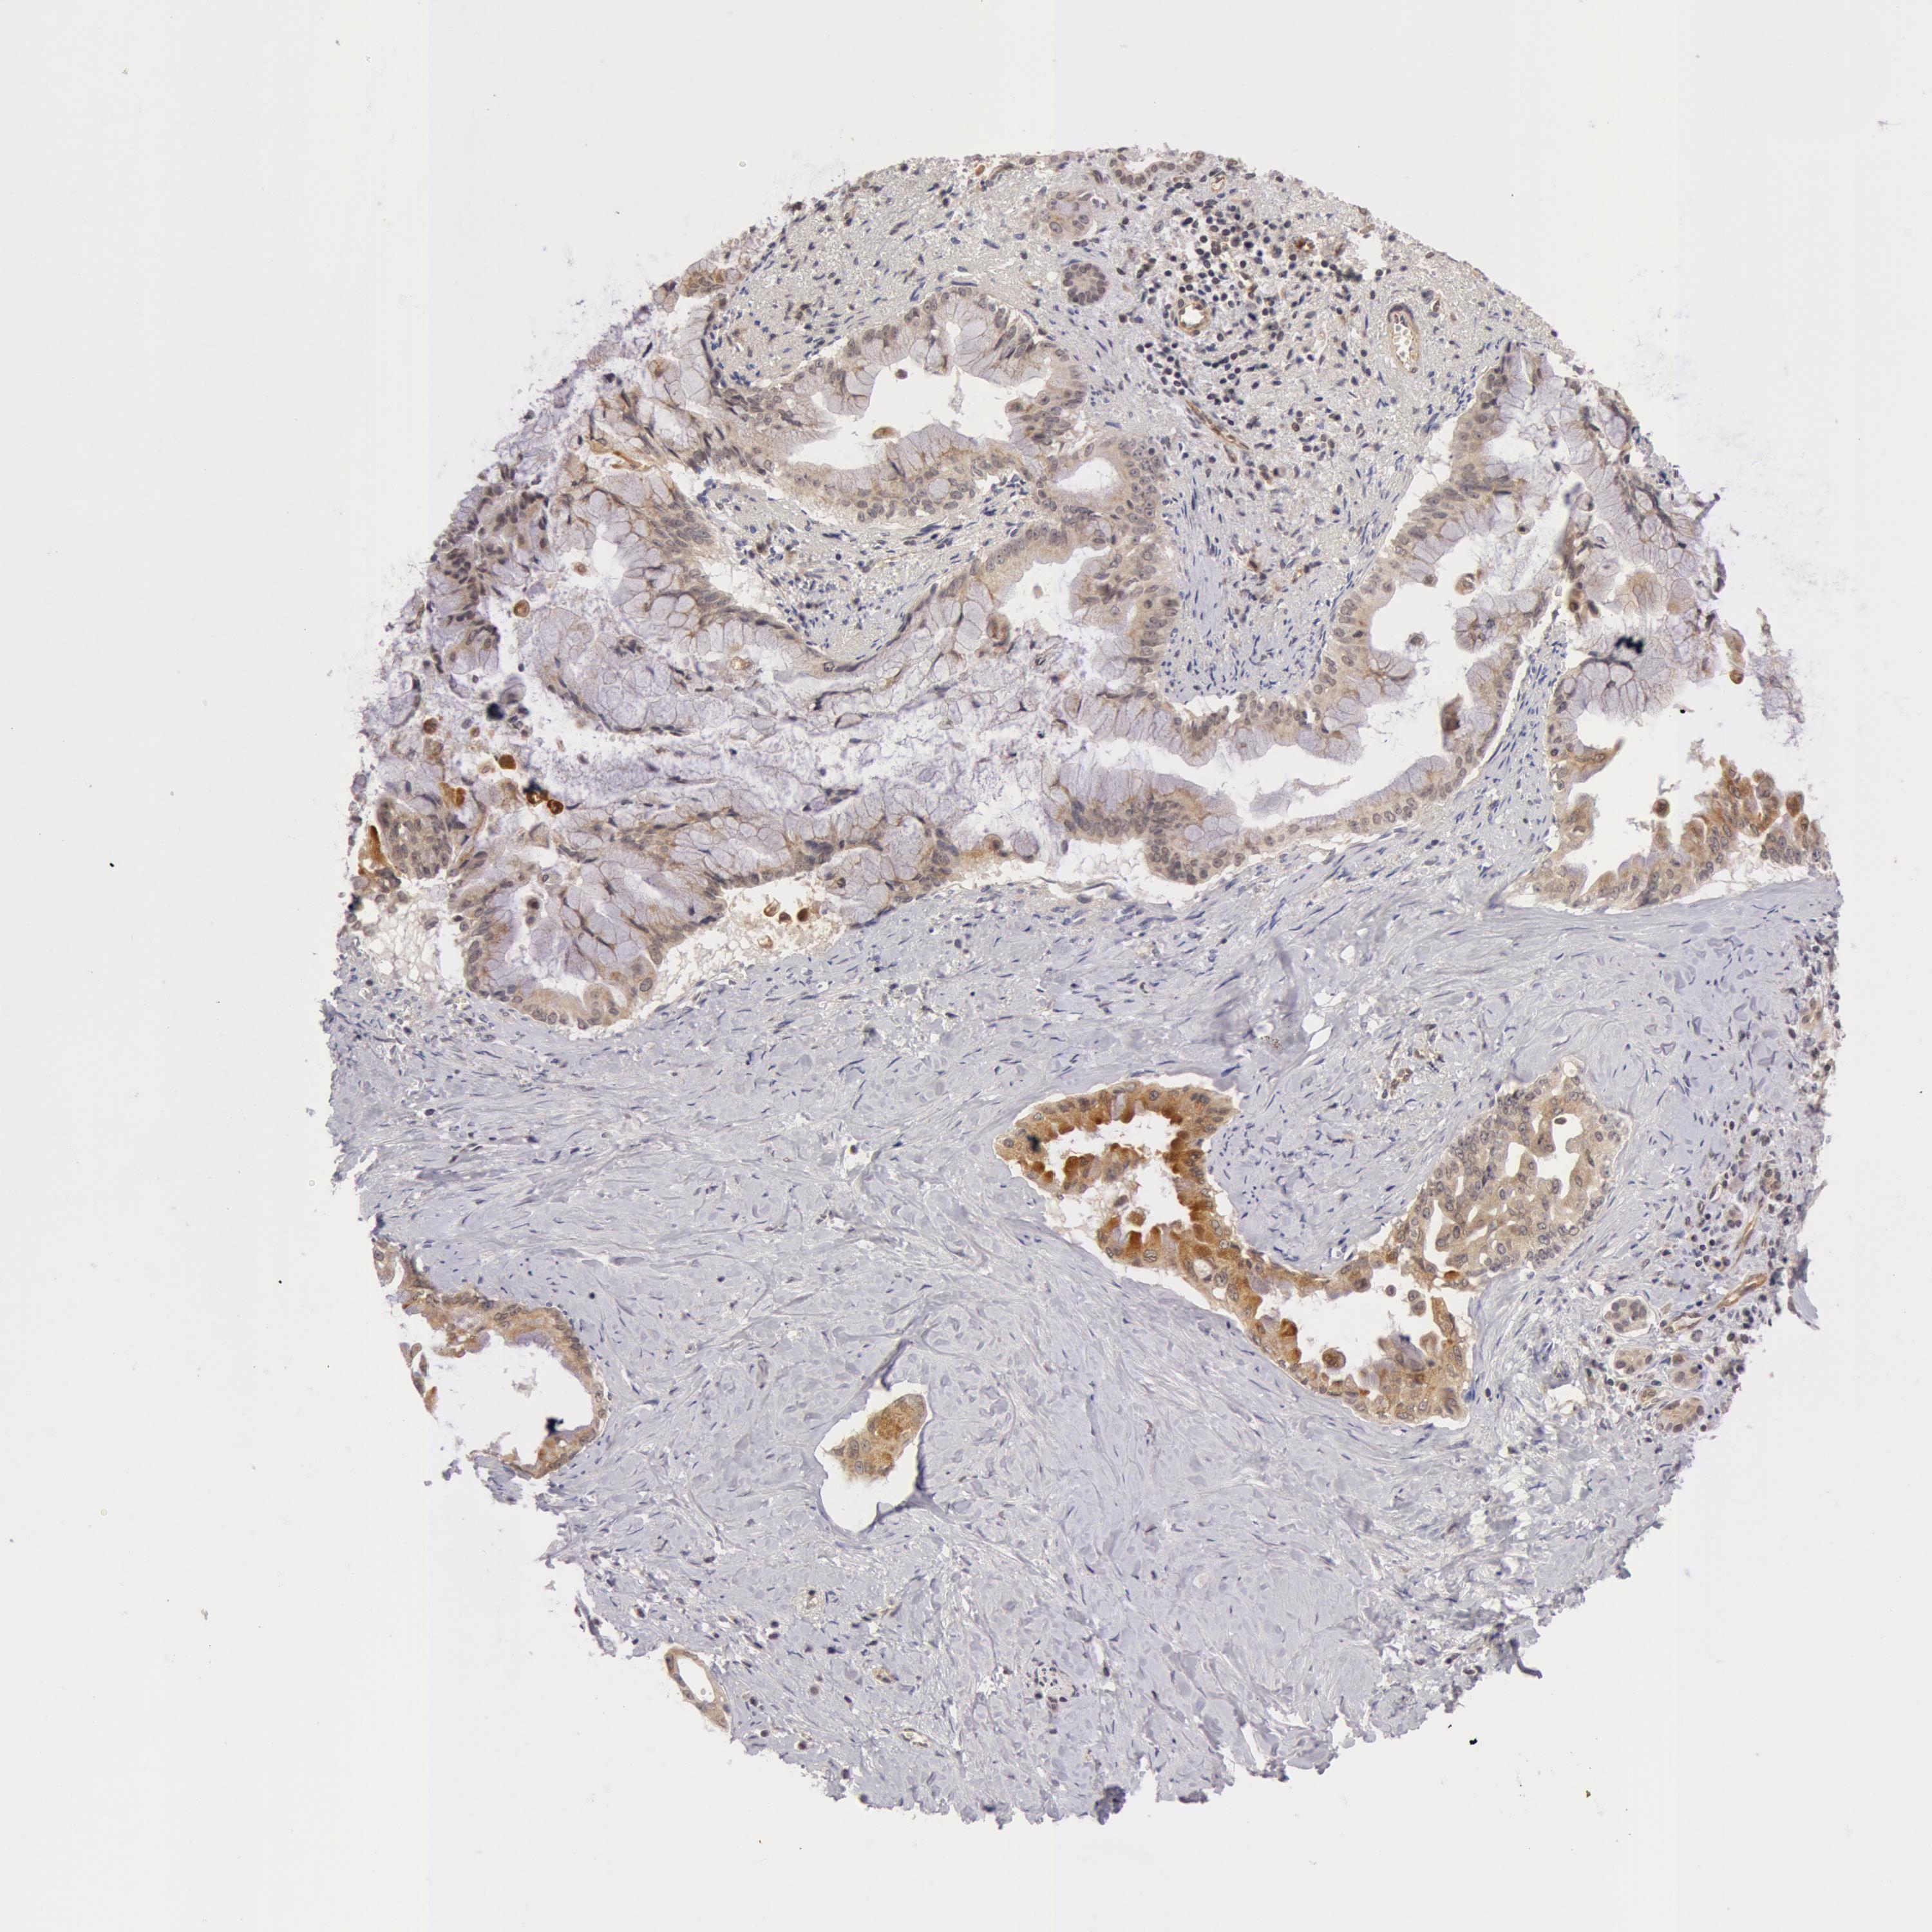

PANCREATIC CANCER - Protein expressioni

A mouse-over function shows sample information and annotation data. Click on an image to view it in a full screen mode. Samples can be filtered based on level of antibody staining by selecting one or several of the following categories: high, medium, low and not detected. The assay and annotation is described here.

Note that samples used for immunohistochemistry by the Human Protein Atlas do not correspond to samples in the TCGA dataset.

Antibody stainingi

Antibody staining in the annotated cell types in the current human tissue is reported as not detected, low, medium, or high, based on conventional immunohistochemistry profiling in selected tissues. This score is based on the combination of the staining intensity and fraction of stained cells.

Each image is clickable and will lead to virtual microscopy that enables deeper exploration of all samples and also displays staining intensity scores, fraction scores and subcellular localization as well as patient and tissue information for each sample.

Antibody HPA001475

Antibody HPA001589

Staining

High

Medium

Low

Not detected

Intensity

Strong

Moderate

Weak

Negative

Quantity

>75%

75%-25%

<25%

None

Location

Nuclear

Cytoplasmic/membranous

Cytoplasmic/membranous,nuclear

Adenocarcinoma, NOS